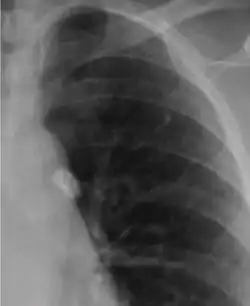

![]() أشعة سينية صدرية لبؤرة غون أشعة سينية صدرية لبؤرة غون | |

تكون بؤرة غون عبارةً عن التهاب ورمي حبيبي في منطقة صغيرة، تشاهد فقط باستخدام الأشعة السينية الصدرية إذا تكلست أو نمت لحد يمكن تمييزها به.[3] نموذجيًا تُشفى البؤرة وحدها، لكن في بعض الحالات وخصوصًا عند المرضى مكبوتي المناعة تتطور لتصبح سل دخني (سميت بسبب الأورام الحبيبية التي تشبه بذور الدخن على أشعة الصدر).[3]